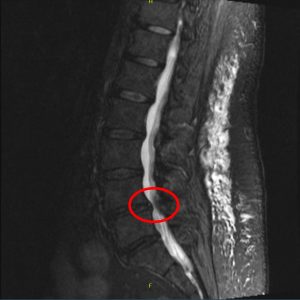

First is sciatica, that we already mentioned. Sciatica is a classic cause of leg pain when walking and standing. The pain is described as “shooting down the leg”. It can be in the buttocks or in the back of the leg. But it can go all the way down to the calf. In fact, with sciatic leg pain it is often hard to find a position that is comfortable. Even in bed. So patients could present with a complaint of leg pain at night more than anything else. Sciatica should not be confused with Spinal stenosis. Spinal stenosis can cause back pain and also leg pain with walking. Patients with sciatica and with spinal stenosis can have leg pain when walking and standing.

Much of the diagnosis is clinical. For instance tight muscles and osteoarthritis. Simple x-rays can also be useful, if the clinical assessment is not enough. Imaging of the spine can help diagnose spinal stenosis. But beware of over-diagnosis. Many patients have findings that are not relevant to their symptoms.